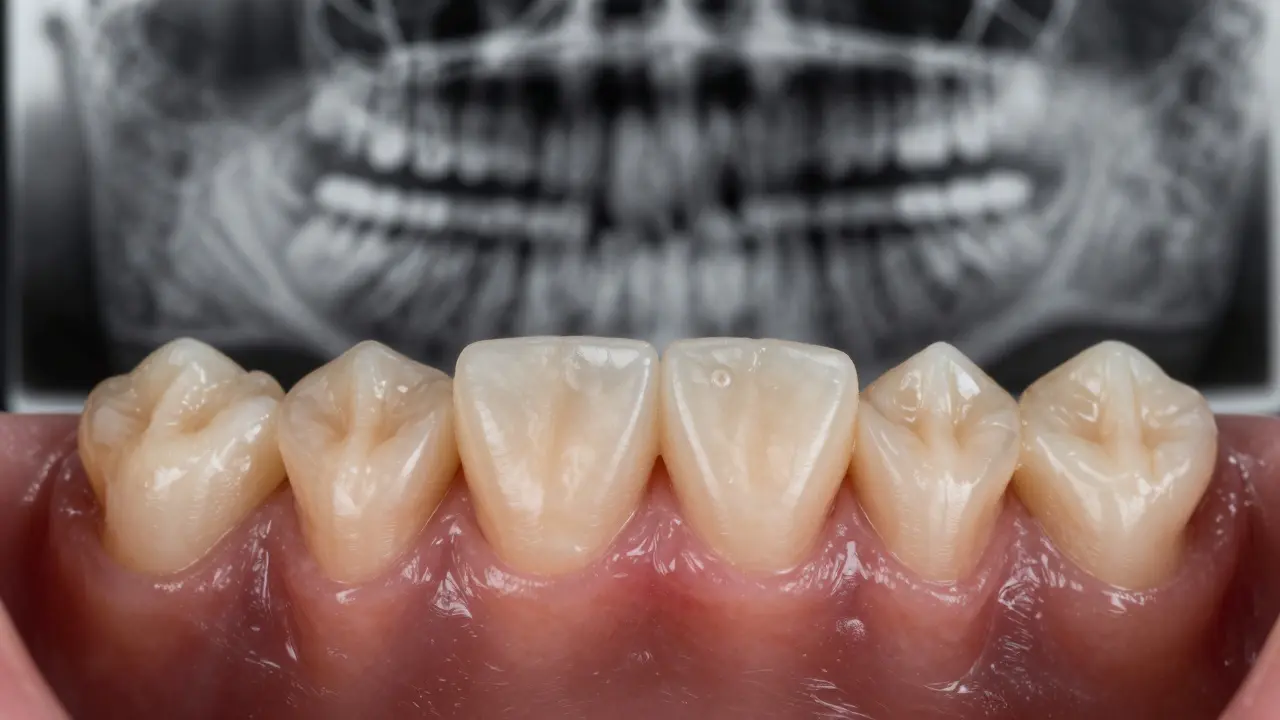

1. Udělá rentgen - nejčastěji panormogram nebo digitální rentgen zubu. To ukáže, zda je kořen poškozený, zda je tam zánět nebo absces.